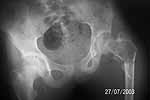

female 12 y ,fell on stairs, 1st xray on admission, 2nd after, 4 days of traction 4kg

I assume pathological fracture through a benign bone cyst. I would work up to be sure benign.

I think you will need to biospy, stabilize (pediatric DHS, I have never used), and graft.